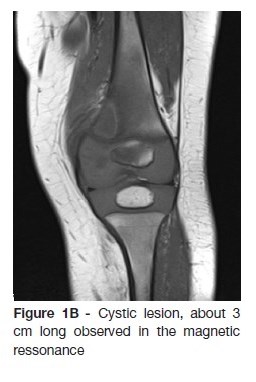

The radiography showed a lytic lesion on the medial femoral condyle (Figure 1A) which was later confirmed by computed tomography and magnetic resonance (Figure 1B).

A previously healthy 12-month-old boy, was observed in the emergency department due to refusal to walk, initially diagnosed as transient synovitis of the hip. After one month, he is again observed due to the persistence of symptoms and fever. On objective examination he presented refusal to walk, reporting no difficulties in crawling. A conventional radiography showed lytic lesion on the medial condyle of the left femur and computed tomography (CT) revealed a probable Brodie abscess. Patient was referred to pediatric orthopedics consultation and then performed a magnetic ressonance that confirmed osteomyelitis with an intraosseous abscess. He was submitted to surgical drainage and four weeks of antibiotic therapy, with no sequelae after one year.